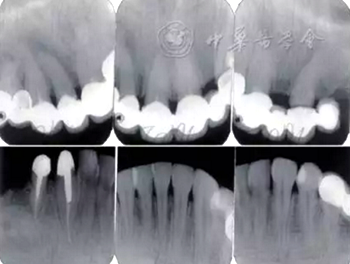

口腔衛(wèi)生狀況一般,菌斑指數(shù)0~2,鄰面少量軟垢;牙齦齦緣鮮紅、水腫、質(zhì)軟,出血指數(shù)2~3,余牙牙齦輕度水腫,出血指數(shù)0~2;全口探診深度2~3 mm,個別位點探診深度達(dá)4~5 mm,鄰面可探及附著喪失;未查及牙齒松動及根分叉病變;烤瓷固定橋修復(fù),冠邊緣密合度欠佳,位于齦下1~2 mm;、唇側(cè)崩瓷,邊緣暴露;上前牙牙齦線不協(xié)調(diào);缺失,右下后牙可摘局部義齒修復(fù),固定橋修復(fù);近中面銀汞充填,近中懸突及繼發(fā)齲;上前牙覆蓋下前牙牙冠的1/2~2/3(圖1)。

圖1 患者初診時臨床照片 A:正面微笑像;B:正面口內(nèi)像

全口根尖X線片示鄰面骨嵴頂影像模糊;根管欠填、根充不致密,、未見根管治療影像,、根尖周可見低密度影像(圖2)。

圖2 患者初診時全口根尖X線片